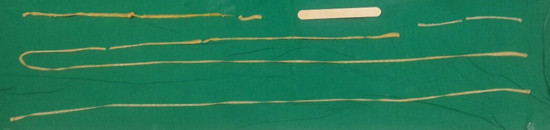

13살 아이의 몸에서 3m짜리 기생충이 발견돼 충격을 주고 있다.25일 한양대병원 소아청소년과의 김용주 교수에 따르면 최근 항문 밖으로 기생충이 나오고 피로감이 심해져 병원을 찾은 13세 남자 환자의 몸에서 3.5m의 광절열두조충이 배출된 것으로 전해졌다.환자의 변에서 광절열두조충 충란이 관찰돼 시약을 복용시켜 기생충을 뽑아냈더니 3.5m 정도까지 배출되다 중간에 끊긴 것으로 알려져 많은 이들에게 충격을 안기고 있다.김 교수는 "중간에 끊긴 것으로 봐서 실제로는 더 길 것으로 예상된다. 국내에서 소아에게 이렇게 긴 기생충이 발견된 사례는 거의 보고 된 바 없다"며 "이 환자가 평소 즐겨 먹던 생선회를 통해 감염됐을 확률이 높다"고 설명했다.광절열두조충은 온대지방이나 북극 근처에 분포하는 촌충의 일종이다.이 기생충은 연어, 숭어, 농어, 송어 등을 숙주로 인체에 들어와 주로 소장에 흡착해 기생하는 것으로 알려졌다.김 교수는 "처방 없이 구입 가능한 기생충 약으로는 광절열두조충 같은 조충류 기생충을 제거하지 못한다. 그렇기 때문에 정기적인 분변검사가 필수"라며 "냉동살균 처리되지 않은 활어회나 생선요리를 즐겨 먹는 사람들은 각별한 주의가 필요하다"고 덧붙였다.한편, 13세 소아 기생충 소식을 접한 네티즌들은 "기생충 길이가 무슨 저렇게 길어" "으 진짜 끔찍하다 기생충" "기생충 너무 역겨워" "저 소아 정말 소름돋았을 듯" 등의 반응을 보였다.[사진 출처=한양대병원]